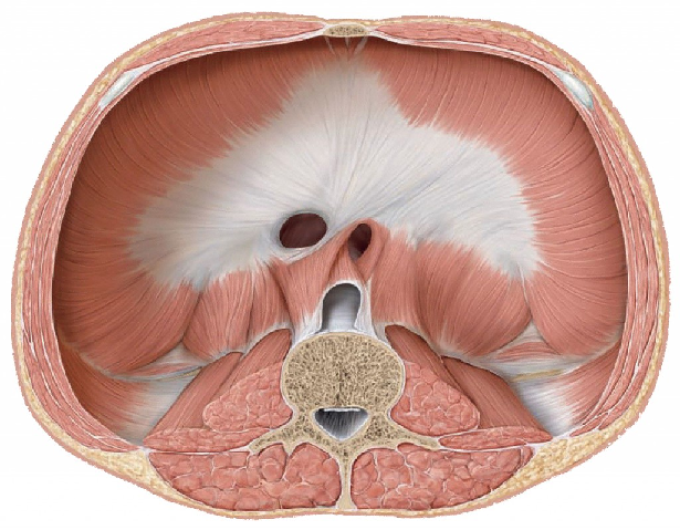

Анатомия диафрагмы и треугольника Бохдалека

Раздел: Визуальный дайджест